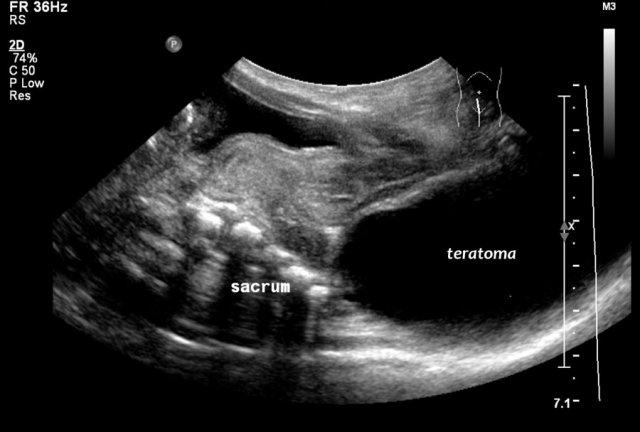

U quái vùng cùng cụt (Sacrococcygeal teratoma)

U quái vùng cùng cụt được cấu thành từ mô đặc, các nang và vôi hóa. Chúng thường được phát hiện qua siêu âm trước sinh và có thể có kích thước rất lớn. Có một hệ thống phân loại như sau:

Bé gái 2 tuổi với khối vùng cùng cụt. Trên siêu âm thấy một tổn thương dạng nang ở phía trước xương cùng, phù hợp với u quái vùng cùng cụt loại 4. Khối u đã được cắt bỏ hoàn toàn.

Sự xâm lấn vào ống sống có thể thấy được trên siêu âm, nhưng MRI cung cấp cái nhìn tổng quan tốt hơn và là tài liệu để so sánh trong tương lai.